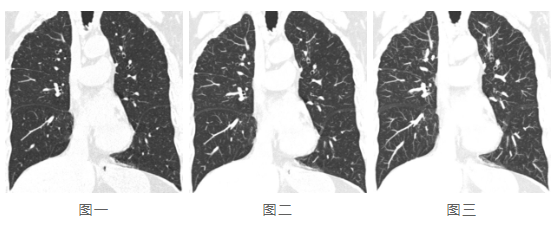

再看下面三張圖:

三張圖的層厚分別為0.5mm、2mm、5mm,隨著層厚的增加,病灶因重疊而被忽略的可能性同步增加。因此,對(duì)于發(fā)現(xiàn)細(xì)小病灶如肺小結(jié)節(jié),層厚調(diào)節(jié)顯然是必備的工具。